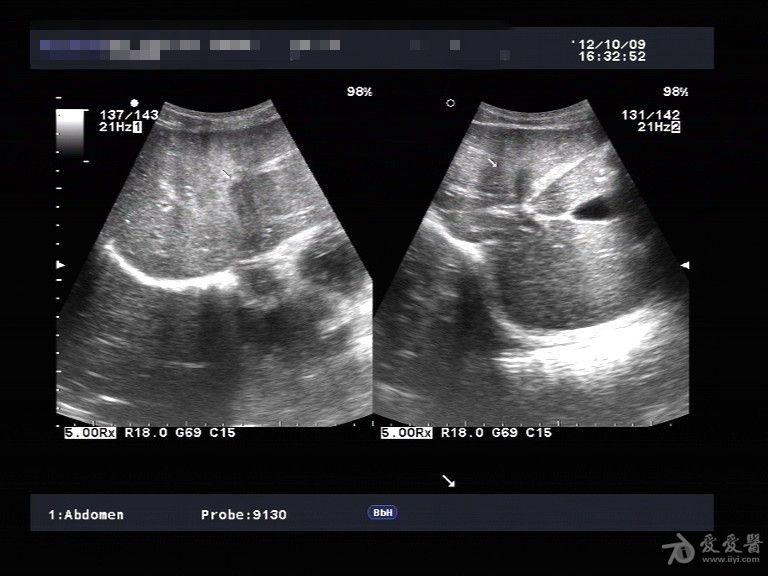

腹 肝挫伤

ct平扫,肝右叶第6,7段背段挫伤,肝被膜下血肿